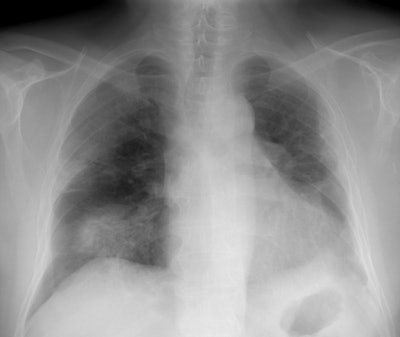

Following antibiotic treatment, the infiltrates and the patients symptoms had worsened (Click image to enlarge)